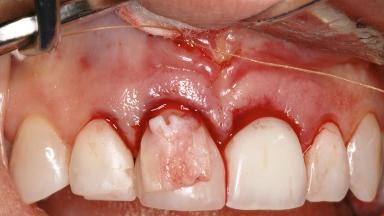

Ridge Preservation and Implant Placement for a Fixed Dental Prosthesis After a Car Accident

It is well known to clinicians that any removal of teeth will, over time, cause the dimensions of the alveolar ridge to be reduced by resorption of the bundle bone and by changes related to external modeling. This development is particularly evident in the crestal region with its thin buccal bone that consists of bundle bone almost entirely. The facial bone will rapidly resorb as blood supply from the periodontal ligament gets disrupted (Araújo and Lindhe 2005). There is no reason why traumatic tooth loss should not have the same consequences. It takes more than achieving implant osseointegration for a treatment outcome to be considered successful. No deficiency of bone or soft tissue is acceptable when an ideal esthetic outcome is the goal. Several articles (Sanz and coworkers 2011; Vignoletti and coworkers 2011) have reported on techniques of improving the alveolar ridge for implant treatment, notably focusing on protecting tissues from resorption.

Soft Tissue Anatomy Intact Defective

Soft Tissue Contour and Volume Slightly compromised